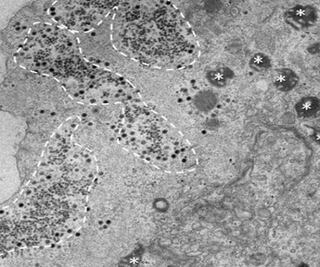

Una investigación brasileña descubrió la presencia de un nuevo virus, nombrado como Yaravirus, con una genética 80% inidentificable, mismo que no es nocivo para el ser humano